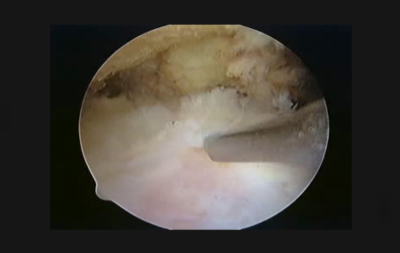

When viewing an intact rotator cuff from the bursal side with an arthroscope

When viewing a torn rotator cuff with an arthroscope

Arthroscopic surgery